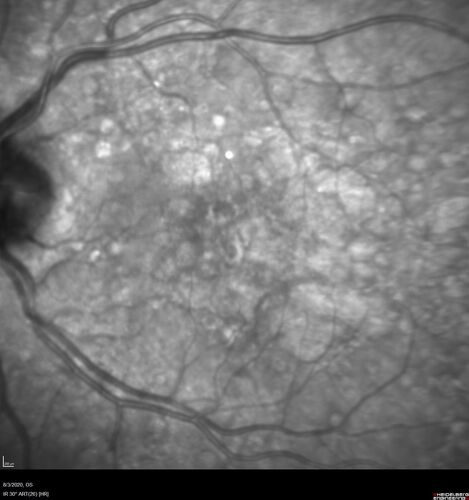

Dry AMD geographic atrophy and cystoid macular edema

79 year old vision is in for a checkup with no visual complaints in the left eye.  This is her better eye.  VA 20/200 OD, 20/50 OS.  3 years ago she had a CRVO in the left eye.  She is also diabetic for 20 years, has carotid insufficiency and anemia.  Left eye shows CME.  This was not treated and the vision improved to 20/40 over the next year although mild edema persisted.